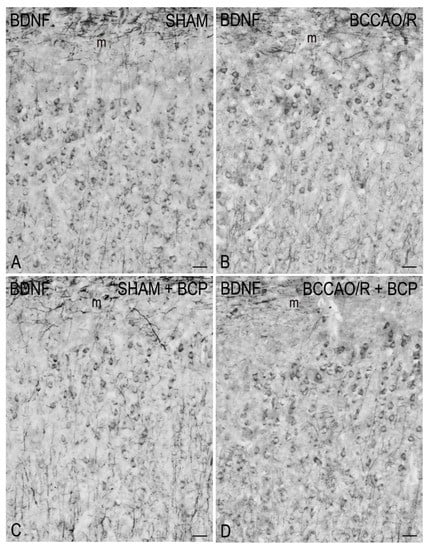

2.2. Immunohistochemistry

3.3. BDNF and trkB in BCCAO/R without and after BCP